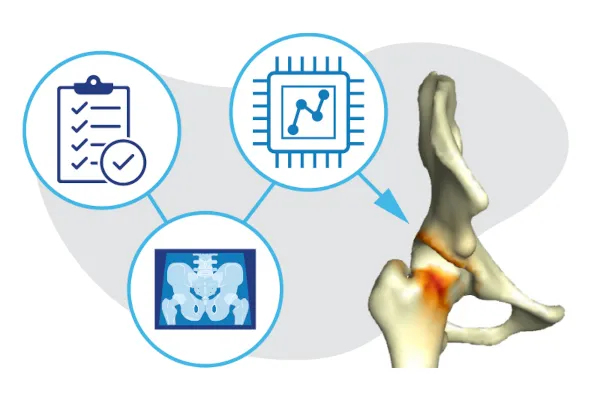

VirtualHip combines AI and 3D imaging to provide detailed information on hip disorders for improved diagnosis and surgical planning.

- More informed diagnosis and treatment of hip deformities: VirtualHip, an application that uses artificial intelligence and 3D modeling to help surgeons diagnose hip deformities and plan surgeries with greater accuracy.